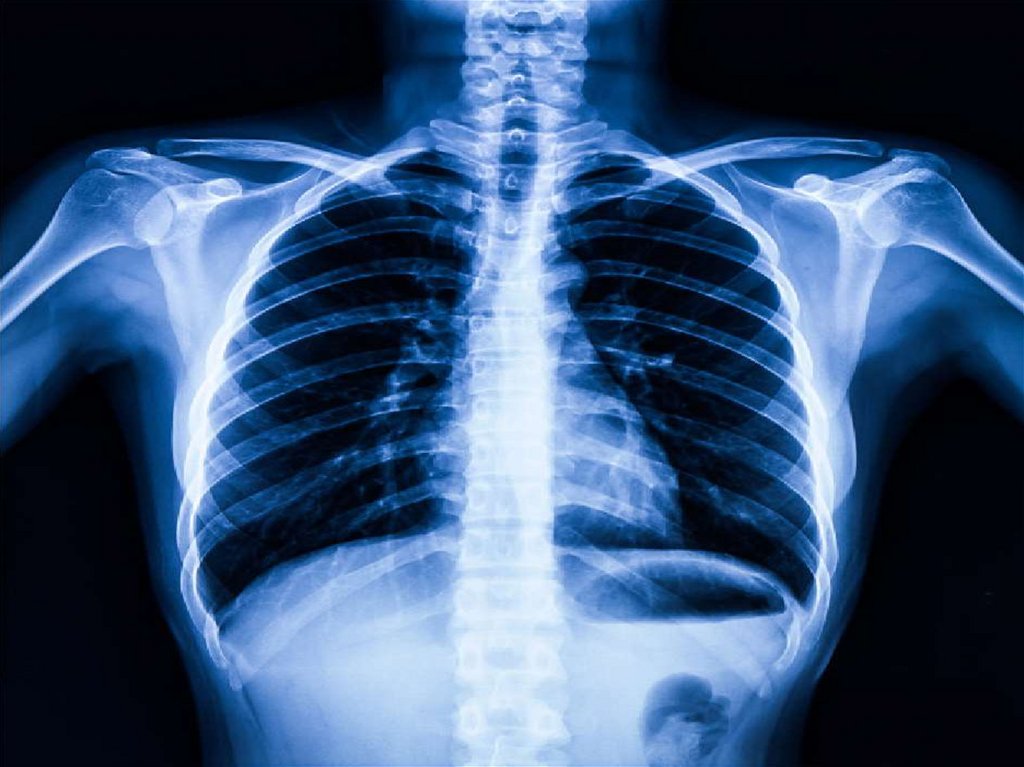

1. Общая характеристика органов грудной полости

2. Грудная полость

это

внутреннее

пространство грудой клетки, ограниченное

внутригрудной фасцией.

Грудная полость содержит средостение, две

плевральных полости с правым и левым

легкими.